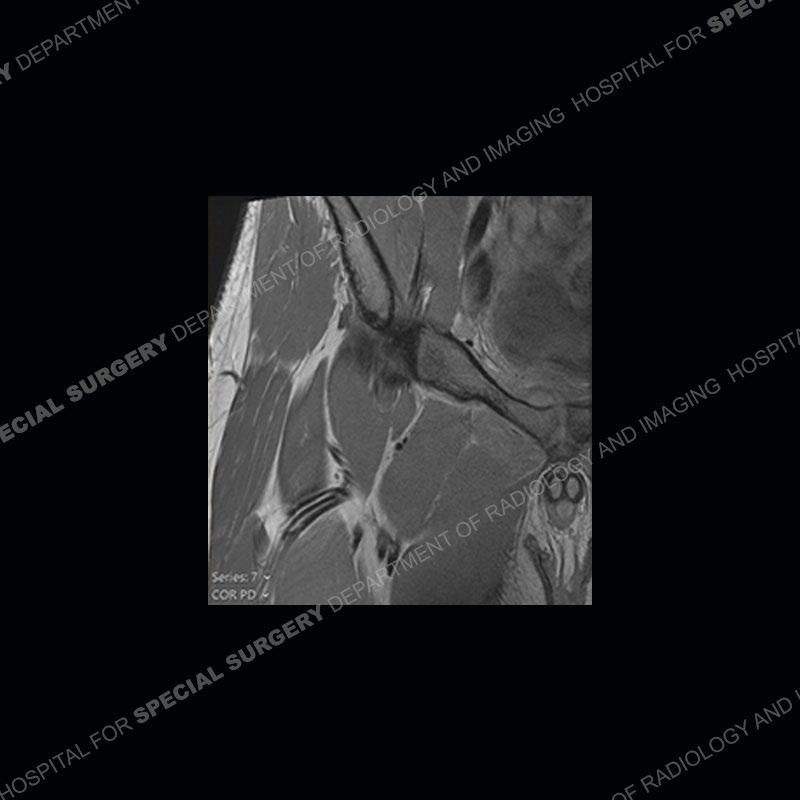

Subsequent MRI in a very short time interval shows markedly increased abnormality of the ramus and increased edema and “mass” of the soft tissue. Post contrast imaging shows multiple, rim enhancing collections of the soft tissue and similar albeit less conspicuous enhancing collection of the ramus.

This case was a bit surprising to all involved given that the young man is otherwise in good health and extremely active in sports. The original thought was this case was going to be an overuse injury or stress fracture. The pubic ramus with the adjacent physis acts as a metaphyseal equivalent and although not frequently thought of would be a reasonable location for infection/osteomyelitis. The first MRI was somewhat confusing as the process did not have an appearance of a stress injury or rectus adductor aponeurosis injury. The degree of edema of the bone and soft tissue together would be odd especially for a sports hernia process. Initially, the thought was of an aggressive process which could be infection or neoplastic. Particularly, the abnormal architecture of the inferior surface of the ramus looked like a destructive process.

The repeat MRI, with the marked degree of increased abnormality of the bone and soft tissue shifted the diagnosis to a high degree towards infection. Even the most aggressive of neoplasms would not have that the degree of change in a 3-day time span. The CT study was shown before the repeat MRI but actually occurred just after the repeat MRI. It helped confirm the destructive process of the ramus and particularly the abnormal architecture along the inferior margin. The patient went on to have a CT guided aspiration of one of the soft tissue collections with 4cc of purulent fluid obtained. A surgical irrigation and debridement of the bone and soft tissue was performed. A PICC line was placed and the patient is currently undergoing IV antibiotic treatment with a possible repeat irrigation and debridement.